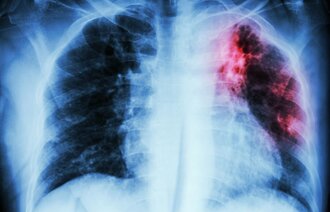

Tuberkulose rammer oftest lungene, men kan også oppstå i andre organer. I praksis er det bare lungetuberkulose som kan være smittsom. Smitte skjer gjennom innånding av bakterier fra luften. Tuberkulose er en relativt lite smittsom sykdom, så smitte skjer vanligvis mellom personer som har nær kontakt over tid (2).